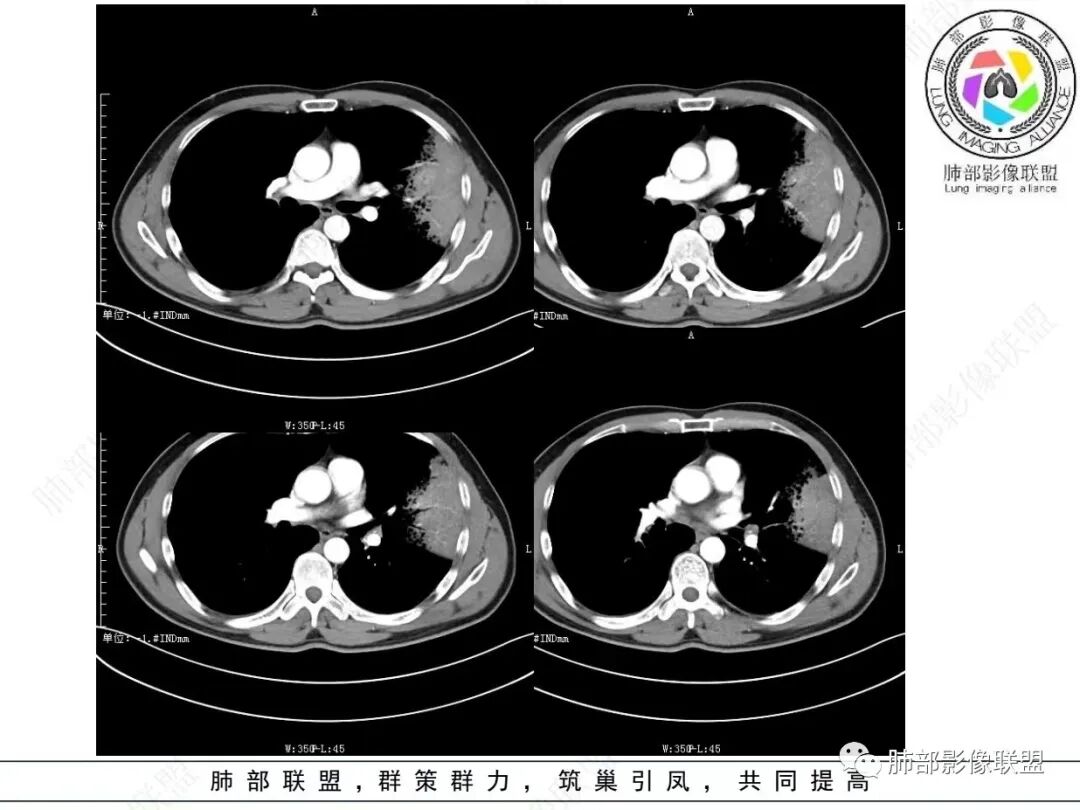

中年男性,咳嗽咳血,影像表现左肺上叶片状阴影,周围可见多发磨玻璃影,病灶内支气管僵硬,增强病灶内可见血管造影征,病灶与胸膜可见栽赃,考虑恶性病变,粘液性腺癌。

左肺上叶胸膜下实变伴周围边缘磨玻璃,其内可见枯枝征及蜂窝,不均匀强化,可见低密度影,血管显示尚可,考虑肺炎型肺腺癌

左肺上叶胸膜下大片状实变区,周围散在磨玻璃影,局部膨隆,界清,近端气管截断,叶间胸膜局部稍膨隆,增强扫描实变区轻度强化,内走形血管僵硬,轮廓毛糙,胸膜栽赃,半年病史考虑恶性,粘液性腺癌

左肺上叶大片状实变密度影,边缘见磨玻璃密度,呈外向内生长,内可见多发支气管影,走行僵直,增强后实变部分明显不均匀强化,血管纤细,考虑粘液腺癌可能大

左肺上叶斑片实变影,内有周边磨玻璃影并小叶内间质增厚,增强实变影内有肺动脉走形,考虑肺炎型肺癌;双肺弥漫分布小结节,细支气管炎?过敏性肺炎?转移?

左肺上叶片状实变,内可见多发空泡及蜂窝影,斜裂上方可见相同病灶由于斜裂阻挡呈重力分布,强化可见血管造影征,双肺弥漫分布气腔结节,临床咳白色粘液痰,考虑粘液腺癌

左上叶大片实变,实变以网格为中心,外向内生长,边界似清非清,实变内见枯树枝征及血管造影征,慢性病史,咳白色粘液痰,炎性标志物基本正常,定性恶性,考虑粘液腺癌

男,46,咳嗽半年,加重10天,白粘痰,偶有痰血。胸部CT:左肺上叶舌叶大片实变影,边缘GGO,长轴沿胸膜及叶裂展开,重力依赖,胸膜叶裂阻隔,内见蜂窝,钱币征,枯枝。强化不均匀,血管造影征。考虑粘液腺癌,鉴别大叶性肺炎、干酪性肺炎等。

实变区内有低密度带,强化偏低,欠均匀

支气管近端通畅,实变区远端堵塞,腔内有粘液栓

血管走形尚自然,没重建血管,没有明显血管受侵

糊墙征   蜂窝征

GGO部分边界清,近实变区密度高

2.左肺上叶大片状混合密度影,未见空洞,实变影主要位于胸膜下,长轴与胸膜平行,实变区内部密度不均、其内可见多发小斑片状低密度影,磨玻璃影多位居肺门一侧,可见网格,磨玻璃影边界多可分辨,重力分布趋势。病灶区支气管显示较为通畅,进入外围实变区渐至消隐。病灶轻度不均匀低强化,病灶区肺动脉显示较良好,未见破坏。

双肺广泛分布微小磨玻璃密度结节影,腺泡结节样分布,密度大小较为均匀一致。